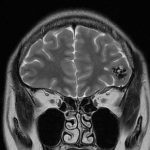

病人….被另一名曾經嚴重腦出血性中風(腦動脈瘤破裂以致嚴重的蜘蛛綱膜下腔出血及曾經瞳孔放大和深度昏迷…其後完全康復)的病人介紹…..帶MRI 底片到我診所尋求第二醫療諮詢….. 其時心情亦愉快…….直到….看了MRI 影像後…..我告訴她真正的MRI檢查結果……她的左前腦額葉上….有一個3cm大的腦動靜脈畸形血管瘤(AVM).. ….亦有最近出過血的跡象…可能是她失去意識和腦癇症的原因。

兩天後….在私家醫院為她做診斷式的動態腦血管造影來確定䐉血液的流動模式後,再進行了4 小時的顯微鏡手術….AVM的計時炸彈完全切除……..在AVM旁邊的腦部亦能看到血鐵黃素的舊有殘留血液。手術後兩天出院。